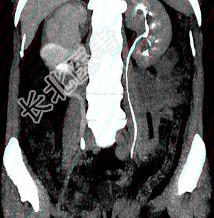

- 多项选择题患者女,44岁, 突发性胁腹部绞痛并向会阴部放射伴血尿一次。如图所示,以下说法正确的是 ( )

A、左肾输尿管未见异常

B、右输尿管内可见沿输尿管走行的高密度影

C、右侧肾盂肾盏扩张

D、右输尿管中上段扩张

E、右输尿管结石